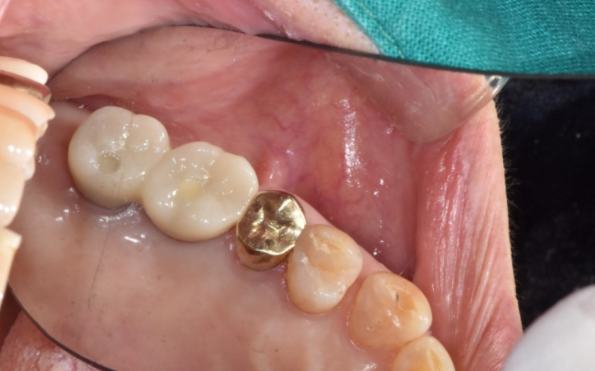

240415

강일역 임플란트 완성 사진입니다.

불편하시던 치아 크라운 빠짐이 해결되셨으니

이제 식사 잘하시고 오래오래 건강하시길 바랍니다.